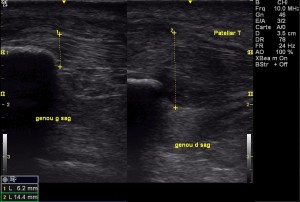

Echographie diagnostique pour la traumatologie articulaire (genou, chevilles, épaule, acromio-claviculaire, etc..):

Les pathologies tendineuses (tendinopathies, bursite, calcifications, ruptures):